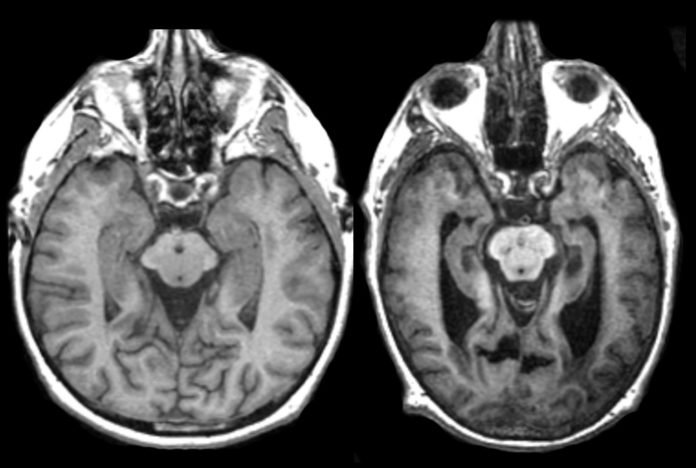

El diagnóstico de las enfermedades priónicas representa uno de los mayores retos de la neurología contemporánea. La ausencia de biomarcadores específicos y la necesidad de técnicas diagnósticas altamente especializadas complican la identificación temprana de estos trastornos. Las pruebas de neuroimagen pueden mostrar patrones característicos, pero la confirmación definitiva frecuentemente requiere análisis del líquido cefalorraquídeo o incluso biopsias cerebrales en casos seleccionados.